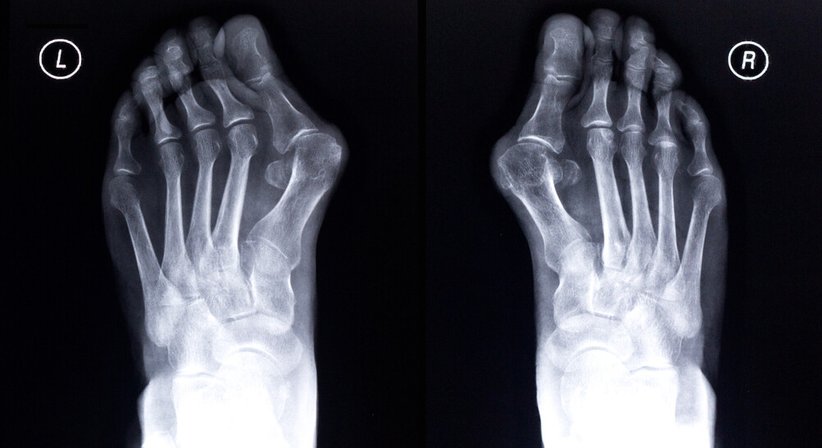

Beim Hallux valgus handelt es sich um eine Fehlstellung des Großzehengrundgelenks, die häufig durch das Tragen von zu engen, spitz zulaufenden Schuhen entsteht und deshalb meist Frauen betrifft. Die Behandlung erfolgt anfangs konservativ. In schweren Fällen hilft nur noch eine Operation, durch die die natürliche Zehenstellung wiederhergestellt wird.